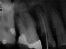

Patientin(66):

2 Aufnahmen sind von 2002 und die dritte vom 01.11.2010

Als Zufallsbefund entdeckter, bis dahin beschwerdefreier apikaler Prozess an Zahn 36. Dessen insgesamt stark verengtes Innenraumsystem gestattete damals in erster Sitzung nur die Darstellung von 2 Kanälen. Wenn intensivstes Weitersuchen erfolglos bleibt, ist dem erfahrenen Behandler irgendwann zumindest so viel über den fehlenden Kanal bekannt: Er kann nicht sehr grosslumig sein und die Weitersuche auf den nächsten Termin zu verschieben ist nicht sehr riskant. Oft genug erlebt, gelingt dann frisch mindreseted und brainrebooted das in Sekunden, was zuvor in 20 min nicht gelingen mochte. So auch hier geschehen, bei der Suche nach dem 3. Kanal.